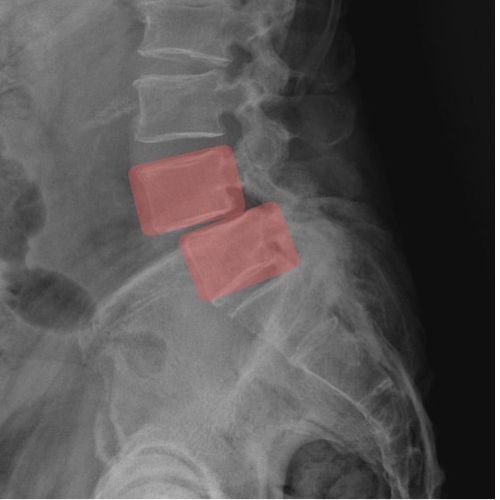

Espondilolistesis Lumbar

Desplazamiento hacia adelante de una vértebra lumbar sobre la inferior. Puede comprimir nervios y producir dolor lumbar, ciática, rigidez, contracturas musculares y dificultad para caminar o mantenerse de pie.